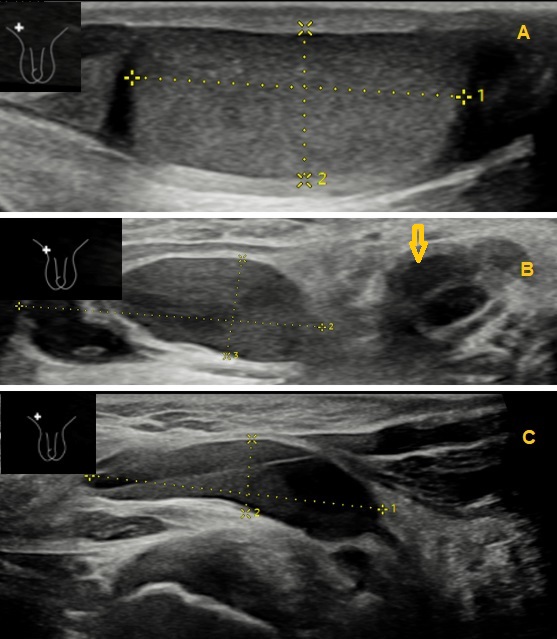

Se realizó una ecografía de manera urgente (Figura 2), en la que se objetivó una malformación linfática macroquística inguinal derecha con posible sangrado y sobreinfección.

| Figura 2. Imágenes de la lesión linfática en la ecografía inguinal realizada en urgencias |

La ecografía testicular fue decisiva para el diagnóstico etiológico definitivo de malformación linfática, entidad clínica poco frecuente y con una presentación muy heterogénea. La ecografía Doppler es la prueba de elección inicial para el diagnóstico de este tipo de lesiones, ya que permite identificar el tipo de flujo, el tamaño y los tejidos a los que afecta la lesión; y, en ocasiones, permite hacer el diagnóstico definitivo sin necesidad de otras pruebas adicionales8,9.